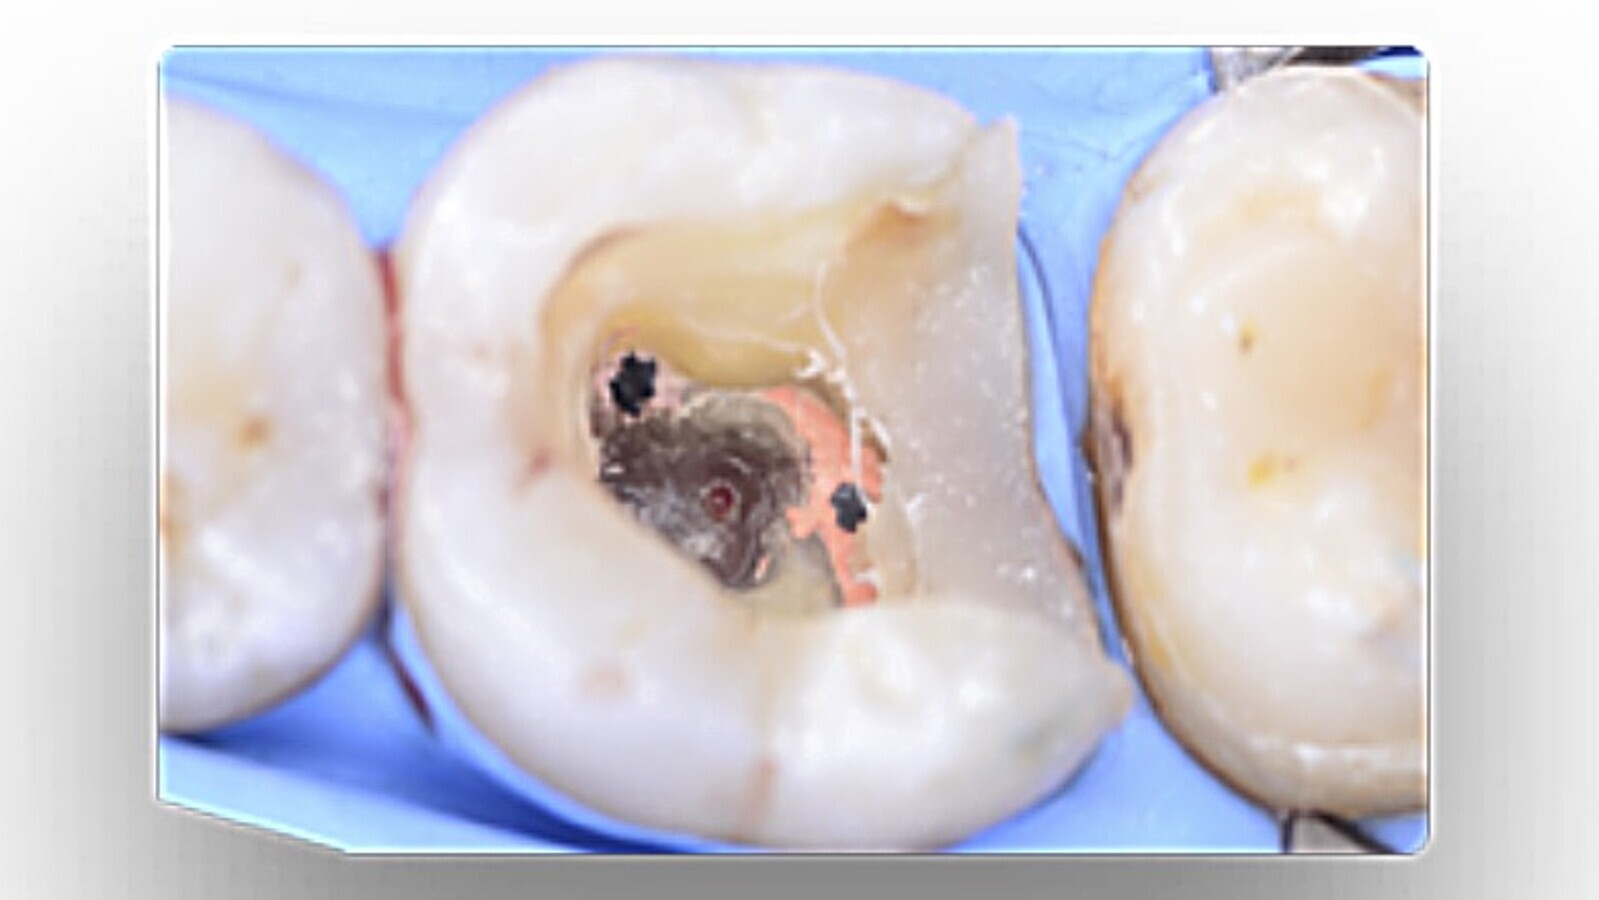

Fig. 3. Imagen clínica inicial del diente 3.6.

Fig. 4. Imagen clínica donde se puede apreciar la perforación en furca.

Durante la apertura cameral se localizó una perforación en furca que se selló con un material biocerámico.